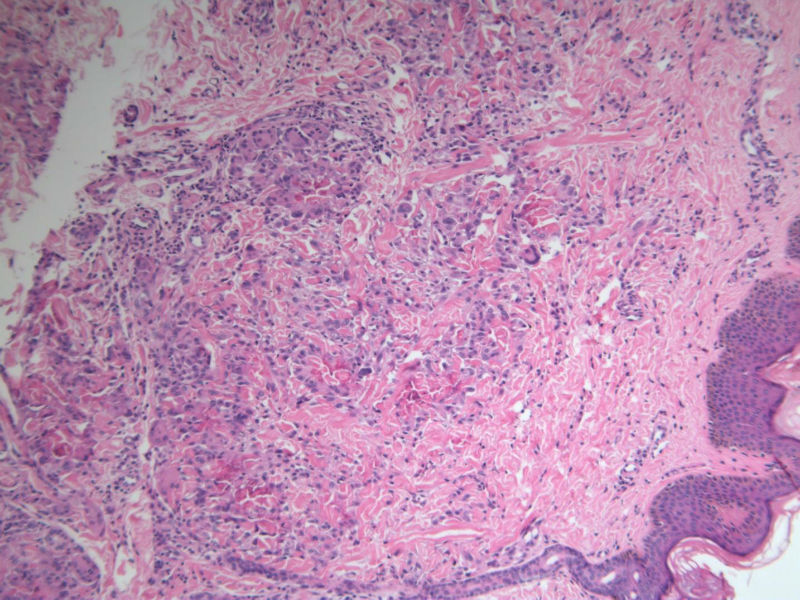

患者 男,8岁,双小腿渐粗红肿伴痒20余天,皮疹渐扩大,且出现硬化萎缩,入院后发现肺吸虫(+)。临床考虑:肺吸虫病硬皮病。请问斑竹大人考虑啥?

• 双小腿红肿伴痒20余天图1

图1

×参考诊断

肺吸虫引起的嗜酸性粒细胞增多性疾病

肉芽肿中央不是凝固性坏死,好像是胶原纤维,否为环状肉芽肿或类脂质渐进性坏死